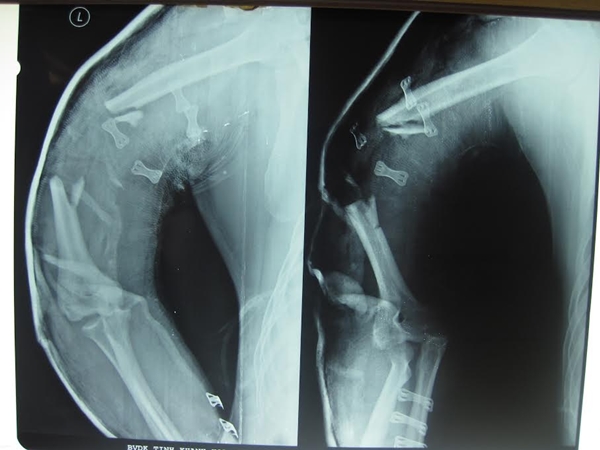

Các bác sĩ Khoa Ngoại chấn thương phối hợp với Khoa Ngoại lồng ngực – Mạch máu Bệnh viện đa khoa tỉnh Khánh Hòa vừa phẫu thuật nối thành công cánh tay của một bệnh nhân, bị máy xay cắt đá cắt gần lìa cánh tay (dập nát cơ, gân, xương và đứt gần hết mạch máu).

Bệnh nhân được cấp cứu vào bệnh viện chiều ngày 15/3, trong tình trạng cánh tay trái bị dập nát, xương gãy lìa, đứt hết gân, cơ, mạch máu... Các bác sĩ đã phải thực hiện ca mổ kéo dài hơn 5 giờ liền để nối gân, nối mạch máu, ghép xương… Sắp tới các bác sĩ sẽ còn tiến hành ghép da (do da bị dập nát hết) cho bệnh nhân.

Bệnh nhân Chung sau khi được nối cánh tay tại BVĐK Khánh Hòa.

Đến trưa ngày 31-3, bệnh nhân đã cử động được cánh tay, mạch tốt, thể trạng toàn thân tốt. Trước đây ông cũng đã từng bị tai nạn lao động mất 3 ngón tay phải.